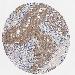

MELANOMA - Protein expressioni

A mouse-over function shows sample information and annotation data. Click on an image to view it in a full screen mode. Samples can be filtered based on level of antibody staining by selecting one or several of the following categories: high, medium, low and not detected. The assay and annotation is described here.

Note that samples used for immunohistochemistry by the Human Protein Atlas do not correspond to samples in the TCGA dataset.

Antibody stainingi

Antibody staining in the annotated cell types in the current human tissue is reported as not detected, low, medium, or high, based on conventional immunohistochemistry profiling in selected tissues. This score is based on the combination of the staining intensity and fraction of stained cells.

Each image is clickable and will lead to virtual microscopy that enables deeper exploration of all samples and also displays staining intensity scores, fraction scores and subcellular localization as well as patient and tissue information for each sample.

Antibody HPA071341

Antibody CAB004602

Staining

High

Medium

Low

Not detected

Intensity

Strong

Moderate

Weak

Negative

Quantity

>75%

75%-25%

<25%

None

Location

Nuclear

Cytoplasmic/membranous

Cytoplasmic/membranous,nuclear

Malignant melanoma, NOS

Malignant melanoma, Metastatic site